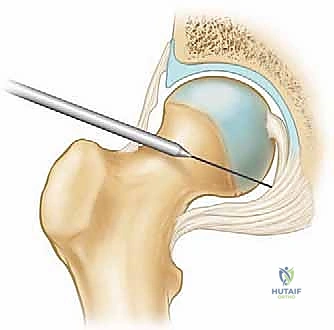

يتم إجراء الجراحة عادة تحت التخدير العام أو النصفي. يوضع المريض على طاولة عمليات خاصة مجهزة بنظام شد (Traction Table). نظراً لأن مفصل الورك مفصل عميق ومحكم جداً، يتم تطبيق شد دقيق ومحسوب على الساق لسحب رأس عظم الفخذ بضعة ملليمترات خارج الحُق. هذا الفراغ الصغير (حوالي 1 سم) ضروري لإدخال أدوات المنظار بأمان دون إتلاف الغضاريف.

2. المداخل الجراحية (Surgical Portals)

بفضل تقنية التدخل المحدود (Minimally Invasive)، لا توجد جروح كبيرة. يقوم الدكتور هطيف بعمل 2 إلى 3 شقوق صغيرة جداً (لا تتجاوز 1 سم لكل منها) حول الورك. من خلال هذه الشقوق (المداخل)، يتم إدخال كاميرا الألياف الضوئية (المنظار) وأدوات جراحية دقيقة للغاية.